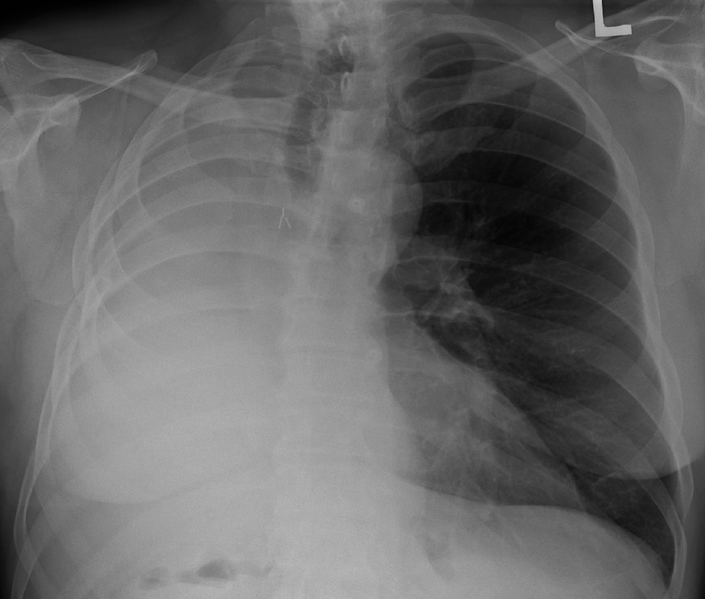

Pneumonectomy

A pneumonectomy is the surgical removal of a lung. The most common reason to remove a lung is lung cancer.

In the below chest x-ray, the right lung has been removed. The half of the chest that looks white instead of black is the missing lung. The remaining lung appears black, and is on the side marked with the “L.”

Immediately after a pneumonectomy, the empty space fills up with air. Then, over several weeks to months, the empty space fills up with fluid (reference).